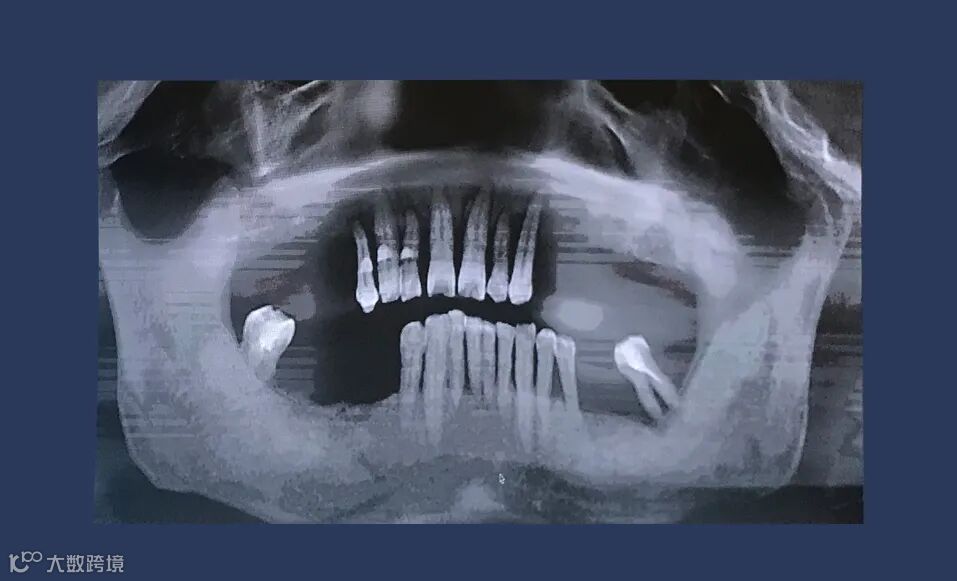

x线检查:上颌余留牙牙槽骨吸收至根尖1/3,预留骨量尚可,骨密度II-III类。

CT检查:后牙余留骨量高度10-12mm,前牙骨高度12-14mm,宽度均大于6mm。